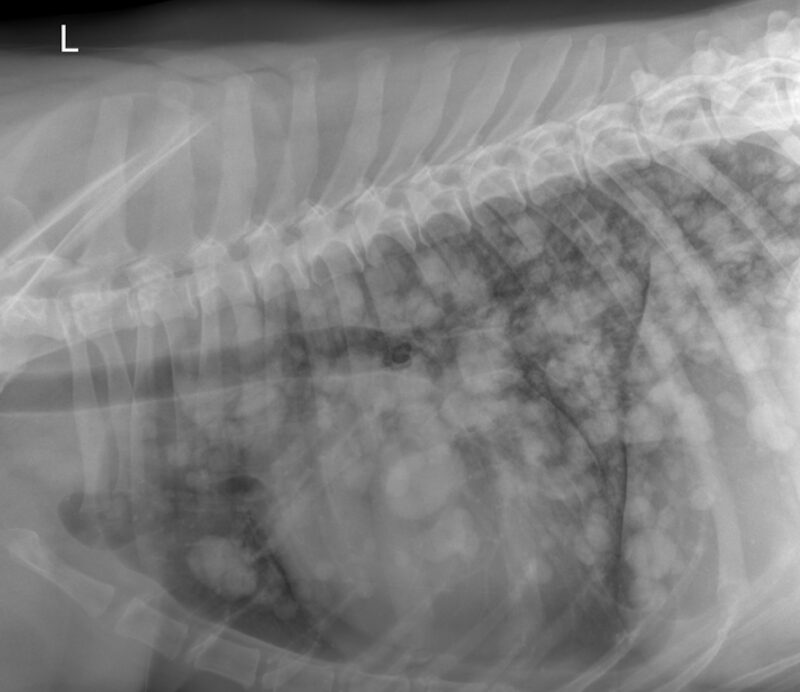

Vielen Dank für die Zusendung der Röntgenbilder. Ein wirklich eindrucksvoller Fall! Es liegen zwei Röntgenaufnahmen des linken Humerus, inkl. Ellbogengelenk, im medio-lateralen, sowie kaudo-kranialem Strahlengang vor. Begleitend besteht eine Röntgenaufnahme des Thorax in dextro-sinistralem Strahlengang (Abb. 1, Abb. 2). Im Röntgenbild der linken Vordergliedmaße zeigt sich im Bereich der gesamten Diaphyse des Humerus, bis in die angrenzenden metaphysären Abschnitte reichend, eine hochgradige, unregelmäßige osteoproliferative Reaktion (blaue Pfeile Abb. 3). Diese periostale Reaktion weist eine heterogene Röntgendichte auf. An ihrer ausgeprägtesten Stelle übersteigt die Proliferation den Durchmesser des normalen Humerus deutlich. Besonders an der kaudalen Humeruskontur besteht hochgradige, laminar geschichtete Knochenneubildung (gelbe Pfeile, Bild links).

Im Thoraxröntgen zeigen sich in allen Lungenlappen multifokale, noduläre Weichteilverschattungen unterschiedlicher Größe, wobei die größte eine Länge von 3,8cm und eine Breite von 2,6cm aufweist (exemplarisch pinke Pfeile). Generalisiert besteht zudem vor allem in den kaudalen Lungenlappen geringgradige (pink gestrichelter Pfeil), sowie im akzessorischen Lungenlappen moderate unstrukturierte Lungenzeichnung. Die Herzsilhouhette ist generalisiert globoid vergrößert (pink gestrichelte Linien). Die kranialen Lungengefäße wirken prominent, sind jedoch kleiner als die proximale Breite im Bereich der vierten Rippe (pinke Pfeilköpfe). Mediastinale Strukturen, Pleuralraum, Trachea, Ösophagus, sowie sichtbare ossäre Anteile stellen sich ohne besonderen Befund dar.